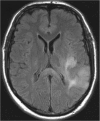

Background and purpose: The splenium of the corpus callosum is the most posterior part of the corpus callosum. Its embryological development, anatomy, vascularization, function, imaging of pathology, possible pathophysiological mechanisms by which pathology may develop and the clinical consequences are discussed.

Methods: A literature-based description is provided on development, anatomy and function. MR and CT images are used to demonstrate pathology. The majority of pathology, known to affect the splenium, and the clinical effects are described in three subsections: (A) limited to the splenium, with elaboration on pathophysiology of reversible splenial lesions, (B) pathology in the cerebral white matter extending into or deriving from the splenium, with special emphasis on tumors, and (C) splenial involvement in generalized conditions affecting the entire brain, with a hypothesis for pathophysiological mechanisms for the different diseases.

Results: The development of the splenium is preceded by the formation of the hippocampal commissure. It is bordered by the falx and the tentorium and is perfused by the anterior and posterior circulation. It contains different caliber axonal fibers and the most compact area of callosal glial cells. These findings may explain the affinity of specific forms of pathology for this region. The fibers interconnect the temporal and occipital regions of both hemispheres reciprocally and are important in language, visuospatial information transfer and behavior. Acquired pathology may lead to changes in consciousness.